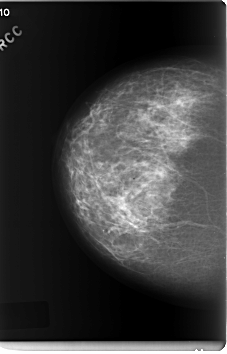

C_0207_1.RIGHT_MLO

RIGHT_CC LINES 6008 PIXELS_PER_LINE 3848 BITS_PER_PIXEL 12 RESOLUTION 50 NON_OVERLAY

RIGHT_MLO LINES 5856 PIXELS_PER_LINE 3672 BITS_PER_PIXEL 12 RESOLUTION 50 NON_OVERLAY